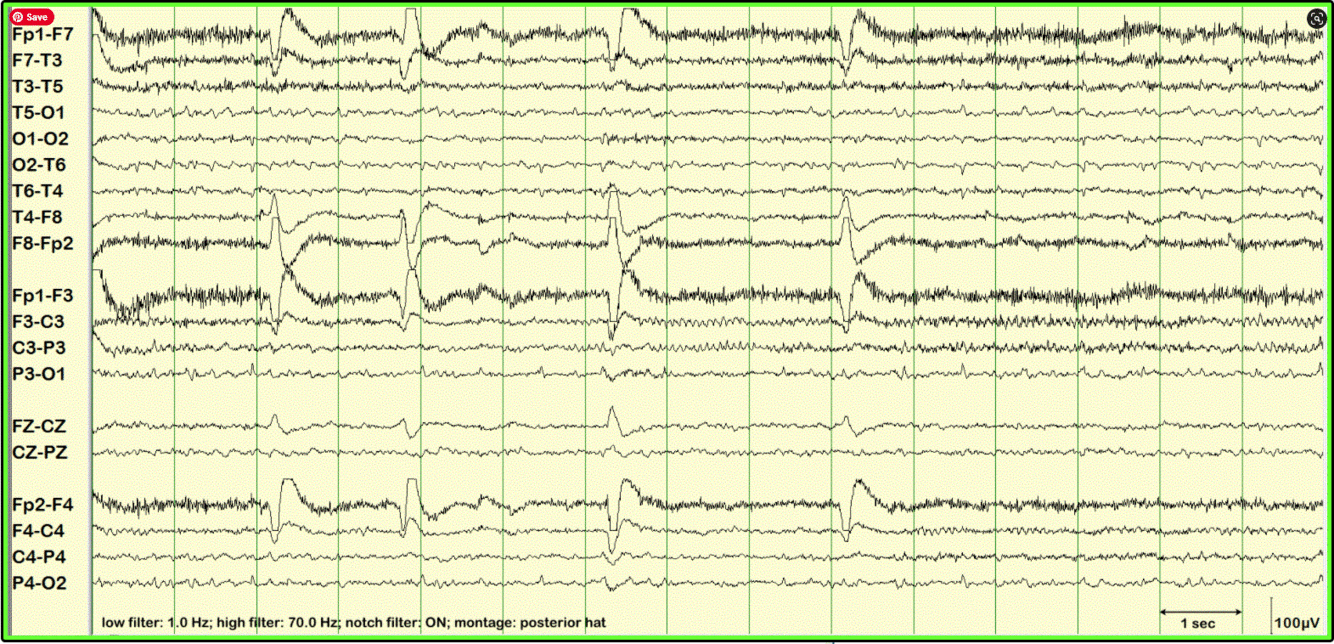

14 and 6 Hz Positive Spikes

• 20-60% of normal population

• 12-20 years

• 6 Hz < 1 y/o

• 14 Hz adolescents (more commonly seen)

• Both can be seen in the same study

• Drowsiness and light sleep

• Posterior temporal and parietal

• Trains of arch shaped waveforms with alternating positive spikey components and negative smooth rounded waveform

• Looks a little like a sleep spindle

• Usually < 2 seconds

• Best seen in referential montages